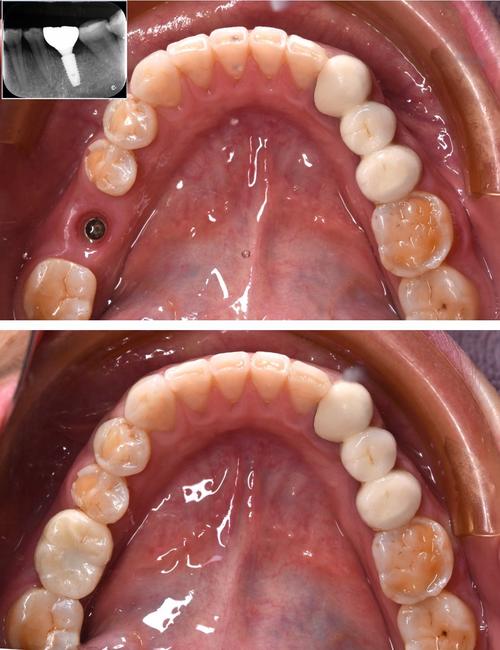

种植牙是通过外科手术将纯钛或钛合金制成的种植体(类似人工牙根)植入牙槽骨内,待3-6个月骨结合完成后,再在种植体上安装基台和牙冠,最终实现功能与美观的修复,其核心优势在于“独立支撑”,不损伤邻牙,且咀嚼效率可达天然牙的90%以上。

- 修复阶段:骨结合后安装愈合基台,2周后取模制作牙冠(全瓷冠、烤瓷冠等),试戴合适后粘固完成。